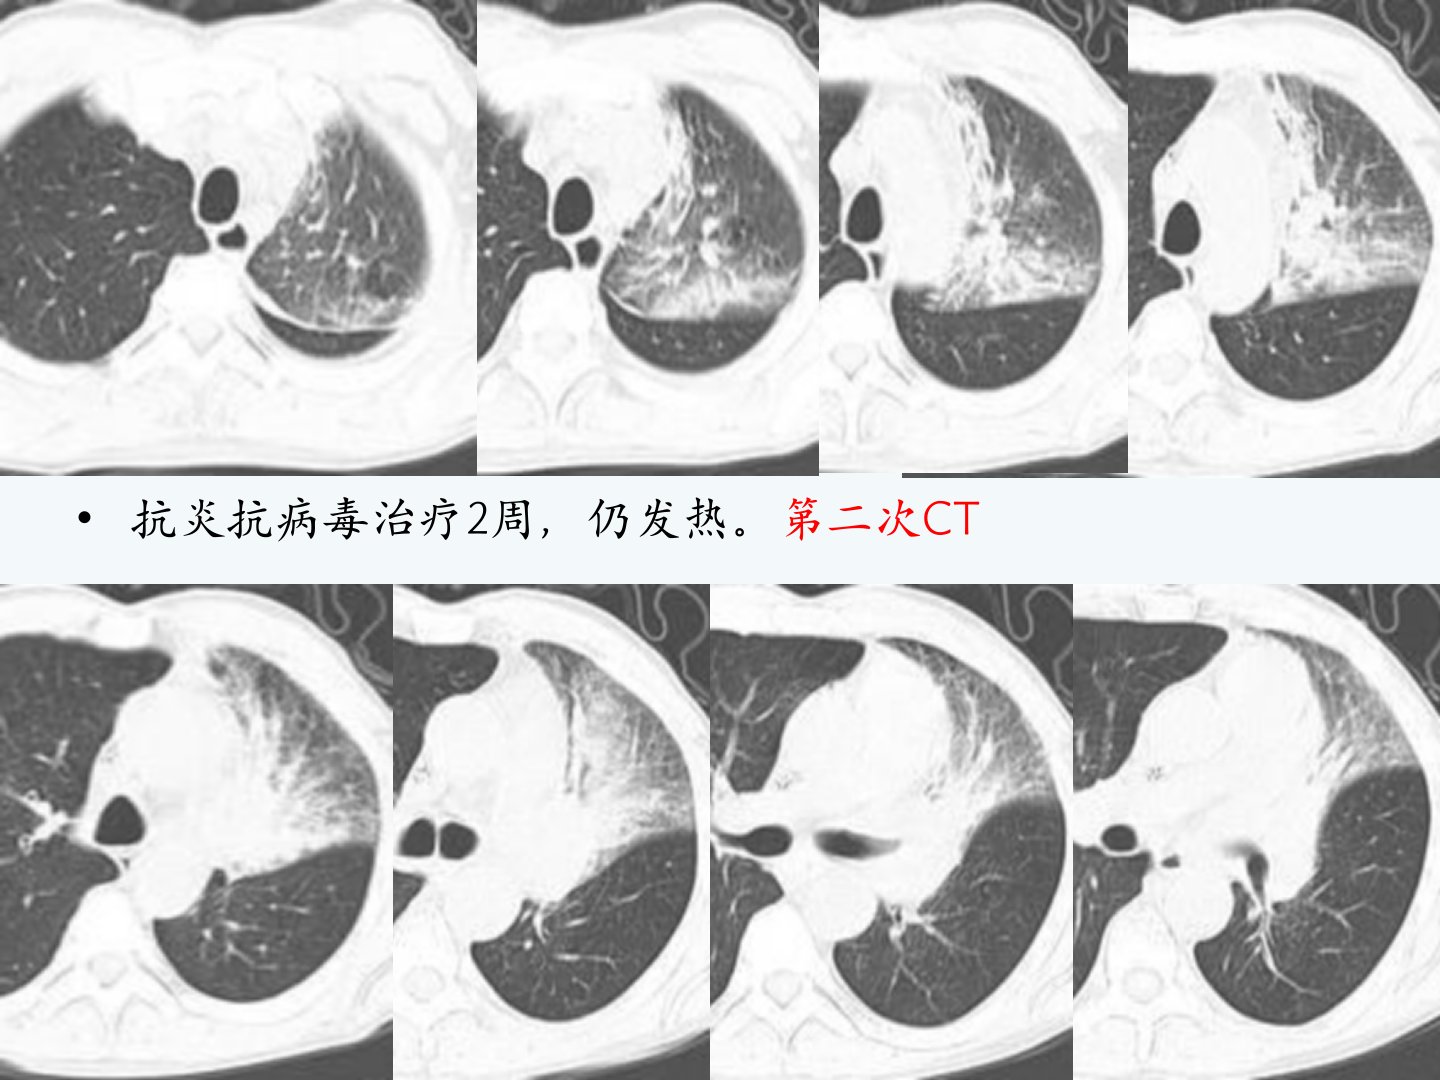

54岁男性急性粒细胞白血病M1型患者化疗后粒缺发热经抗炎抗病毒治疗无效。CT复查结合纤支镜病理确诊为侵袭性支气管曲菌病。曲霉菌病是真菌感染中最常见的一种急性白血病患者发病率高误诊病死率高常见于免疫力低下、长期使用广谱抗生素等人群。诊断标准包括宿主因素、临床特征、病原菌检测等。肺曲菌病根据宿主免疫反应分为寄生性、过敏性、半侵袭性、侵袭性4种类型。侵袭性曲菌病是最常见的机遇性肺部真菌感染影像表现为早期胸膜下密度增高结节实变影后出现晕轮征1015天后出现空洞或新月征。血管侵袭性曲菌病表现为伴有晕征的小结节影抗真菌治疗后空洞形成“空气半月征”;气道侵袭性曲菌病占侵袭性肺曲菌病的1030病理为小气道壁液化坏死及中性粒细胞浸润分为气管支气管炎型、细支气管炎型、支气管肺炎型。肺部曲菌病类型与机体免疫状态有关CT表现有差异典型表现者可准确诊断不典型者需结合临床或病理确诊。